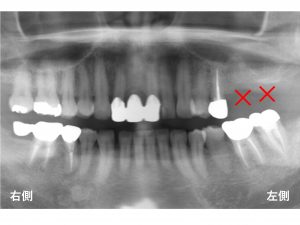

以下が治療が終わった後の状態です。

これで左側の奥歯でもしっかりと噛むことができるようになりました。